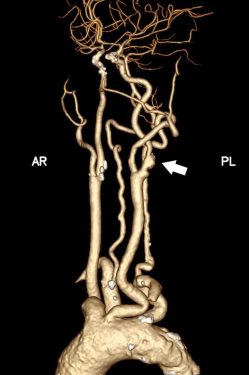

据悉,患者张某(化姓)因反复头晕就诊,检查后确诊为左侧颈内动脉重度狭窄,且主动脉弓为III型弓,颈总动脉明显迂曲,且左侧颈动脉分叉位置较高,属于颈动脉狭窄治疗中较为复杂的解剖类型。若采用传统经股动脉颈动脉支架置入术,导管通过主动脉弓及扭曲血管难度大,脑栓塞风险高;若行颈动脉内膜剥脱术,则会因为分叉位置高、术野暴露困难,手术创伤和技术难度也明显增加。

针对患者复杂病情,烟台毓璜顶医院血管外科团队在车海杰主任的带领下,开展了多轮术前讨论。在与患者及家属充分沟通后,最终确定采用国际前沿的TCAR技术实施治疗。手术当天,团队通过颈部小切口精准暴露颈总动脉,快速建立反转脑血流保护系统,在全程有效脑保护下完成病变段支架精准植入。术中造影显示,患者狭窄的颈内动脉恢复通畅,支架位置贴合理想,脑部供血得到显著改善。术后患者恢复顺利,无任何新发神经系统并发症,头晕等不适症状明显缓解,目前已顺利康复。

手术前后

宋富波表示,TCAR是近年来国际上治疗颈动脉狭窄的创新微创技术,融合了开放手术与腔内介入的双重优势。与传统术式相比,该技术通过建立反转血流脑保护系统,能有效减少操作过程中栓子进入脑循环的风险,同时具备切口小、创伤轻、恢复快等特点,尤其适用于高龄、合并多种基础疾病或解剖条件复杂的高危颈动脉狭窄患者,从源头上提升了手术的安全性和有效性。